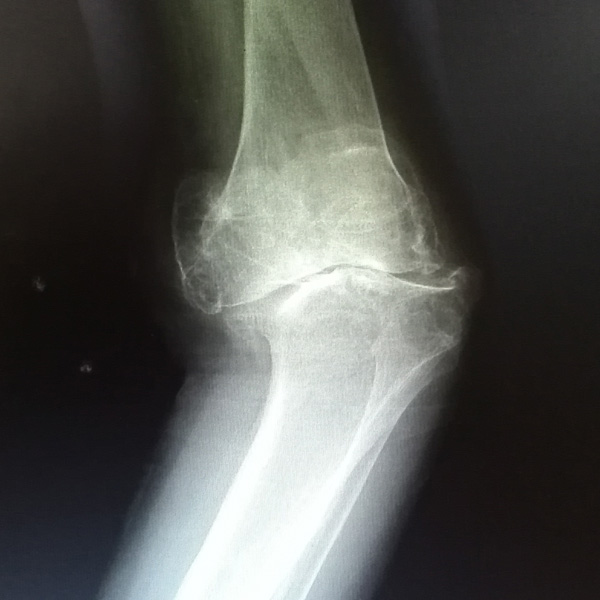

骨肉瘤手術

患者張某,女,14歲,診斷為“左股骨遠端骨肉瘤”,當地醫院因為醫療技術和能力的限制,只能考慮截肢手術。患者家屬通過平臺推薦,指定到哈......